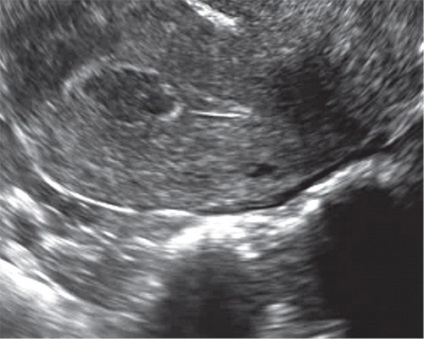

Ez részben annak a ténynek köszönhető, hogy minden esetben a nyaki polipok jellemző a kis méret és egy vereség. Emellett, például a mirigyes polipok általában nem látható ultrahang-letapogatással annak a ténynek köszönhető, hogy nem csak ehonegativnoe mirigyállományt polipok összeolvad a kép a méhnyak és a myometrium lehet megkülönböztethetetlen Ov. Nabotii (ábra. 1), közel az endocervikális, hanem azért is, mert a nyálka a lumen a méhnyak. Ugyanakkor a kép ehonegativnoe folyadék (nyák) hangsúlyozza a kontúrok a visszhang-pozitív kóros oktatás, ami jól látható a hangkép. Mivel van intraluminális polip növekedés és részben lezárja a méhnyakon, fölött vagy alatt a váladék felhalmozódhat, ami megkönnyíti az észlelési az patológiás formáció (ábra. 2). Kétséges esetekben célszerű megismételni a tanulmány periovulyatornoy fázis (késő proliferatív és korai kiválasztó), ha van egy fiziológiai számának növekedése a méhnyak nyálkahártya és közepette anechoic tartalma jól láthatóvá polipok. Folyékony tartalom néha lehetővé teszi, hogy láthatóvá tegyük a polip lába, mint lineáris echogén szerkezet vagy annak szubsztrátja [3, 5]. A átmérője a lumen a csatorna fokozatosan kiszélesedik során proliferatív fázisban, tetőzik ovuláció ideje (1,1 mm között 4-7 nap, és 1,8 mm-es napon 11-14). Miután ovuláció csatornát szűkíti a lumen szinte teljesen (legfeljebb 0,5 mm), a legaktívabb - a korai kiválasztó fázisban [4].

Ábra. 2. Egy polip üregében a méhnyakon.

Érintkezése során ehometrosalpingografii alkalmazásával végzik, mint kontraszt steril sóoldatban is lehetővé válik láthatóvá a kis polipok az endometrium és az endometrium összenövések (ábra. 3). Az akusztikus alapja a lehetséges nem-invazív és ehogisteroskopii ehotservikoskopii teremt serometra, például posztmenopauzális elzáródás külső os (ábra. 4), vagy, amint azt a fentiekben megjegyeztük, a fokozott nyálka termelődés a cervikális végén a proliferatív fázis a menstruációs ciklus. Mivel a váladék az időszakban bizonyos esetekben állnak vizualizációs és polipok, lokalizált a külső os. Hematometra és / vagy gematotserviks, mert a szervezet folyamatai vérrögök kevésbé informatív, mint ennek fényében fibrin vérrögök és polipok nehéz lehet megkülönböztetni a normál B-mód (ábra. 5, 6).